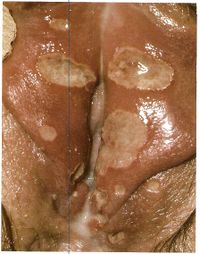

Chancroid

1. cause: H ducreyi

2. multiple painful lesions

3. painful inguinal lymphadenopathy (buboes) that may become an abscess and rupture

Chancroidmale.jpg Chancroidfemale.jpg